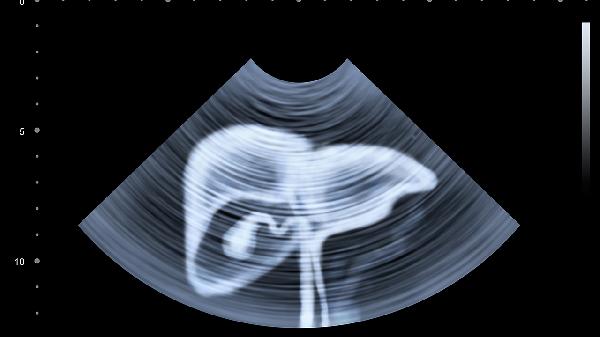

腹水需要引起重视,可能与肝硬化、心力衰竭、肾病综合征等疾病相关。这类情况常伴随下肢水肿、呼吸困难等症状,需通过超声检查确诊并及时治疗。妊娠期女性出现腹部膨隆属于正常生理现象,但需通过超声排除异常妊娠。肿瘤性疾病如卵巢囊肿、子宫肌瘤或腹腔肿瘤可能导致腹部进行性增大,通常需结合影像学检查和肿瘤标志物筛查明确诊断。